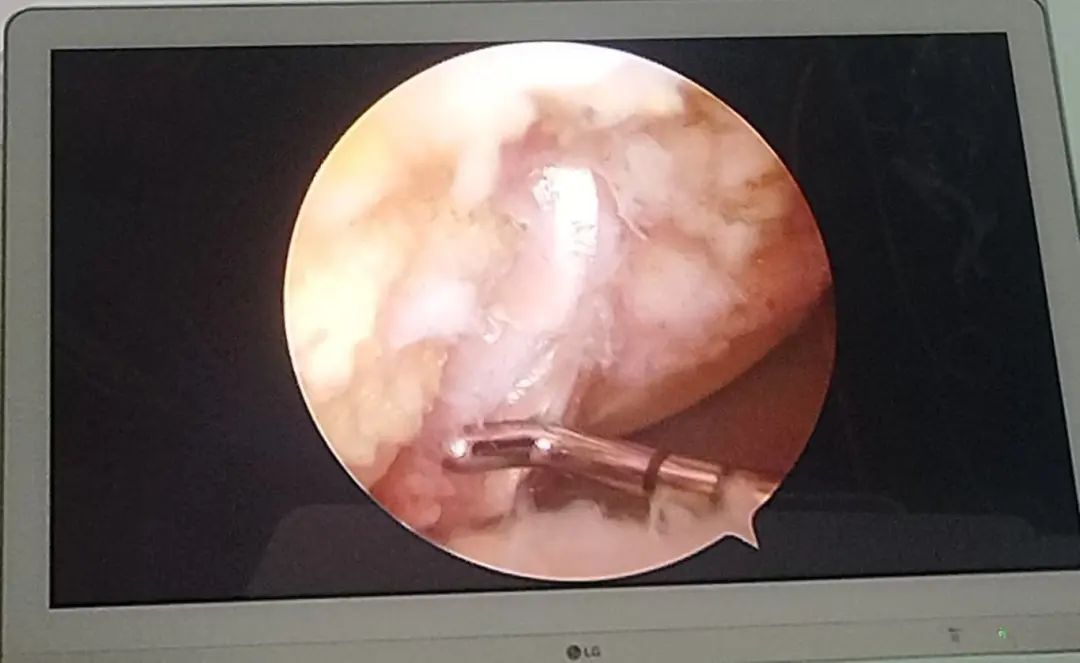

冉先生,52岁,左膝关节疼痛3月有余,据了解万山区人民医院帮扶专家王刚对关节疾病治疗医术精湛,慕名而来。入院后,经检查发现患者左侧膝关节外侧半月板III度损伤、左侧膝关节前后交叉韧带损伤。考虑患者身体情况,经过术前综合评估,最终决定通过“滑膜+半月板+韧带”联合重建微创的方式,让患者受损膝盖能够更快恢复。术后病人安全返回病房,在骨一科医护人员的精心照料下顺利出院。

微创护航,重获健康。微创手术具有创伤小、恢复快,疤痕小、更美观等特点,能够极大缩短患者住院时间,减轻患者负担。未来,骨一科将继续秉持以患者为中心的服务理念,以最小损伤解决患者病痛,让患者“轻”松恢复健康。